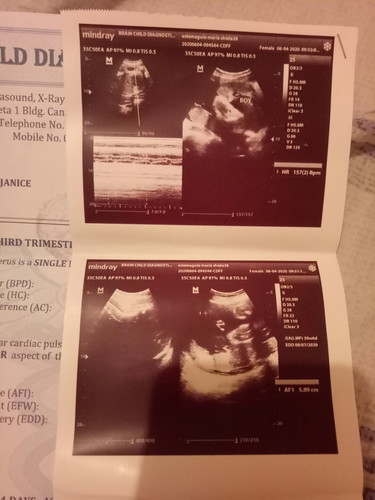

hi mga mommies, pasuyo naman pano ba nalaman na boy baby ko, di ko kasi makita yung part namay egg siya eh, gusto ko lang makasure kung boy ba talaga si baby, thank you

pagmay lawit un baby boy un nakita mo ung boy na nakasulat sa utz mo . ayun ung lawit pag girl kase guhit lang